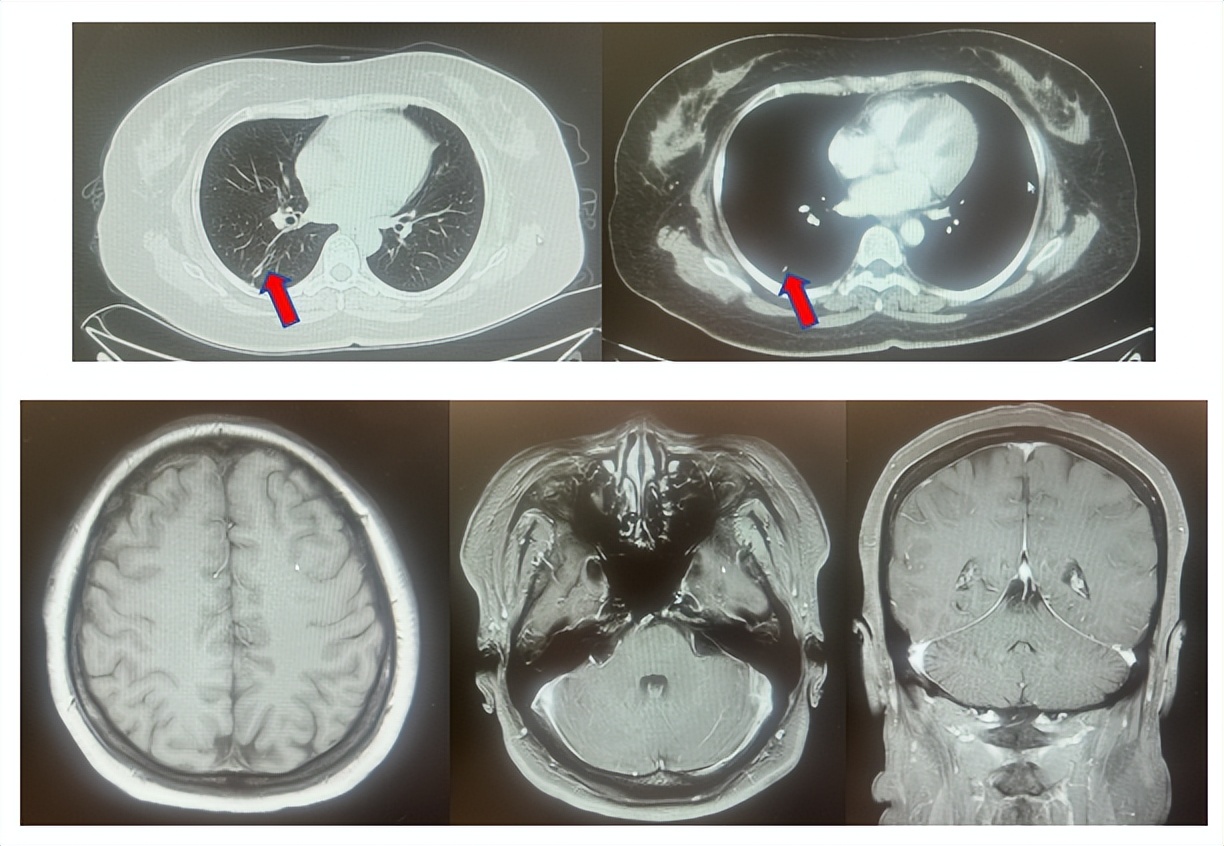

1.2影像学检查(图1)

肺+全腹CT:右肺下叶占位、伴纵隔多发淋巴结肿大,恶性可能性大;右侧心膈角结节,左侧胸廓入口淋巴结增大。

脑MRI:左侧顶叶及右侧小脑结节,转移可能性大。

图1:上两图分别展示基线肺CT肺窗及纵隔窗影像,下三图表示脑MRI影像。红色箭头指示病灶位置,分别为右肺肿物、右侧肺门转移病灶、左侧顶叶病灶、右侧小脑病灶及冠状面上的颅内两个病灶。